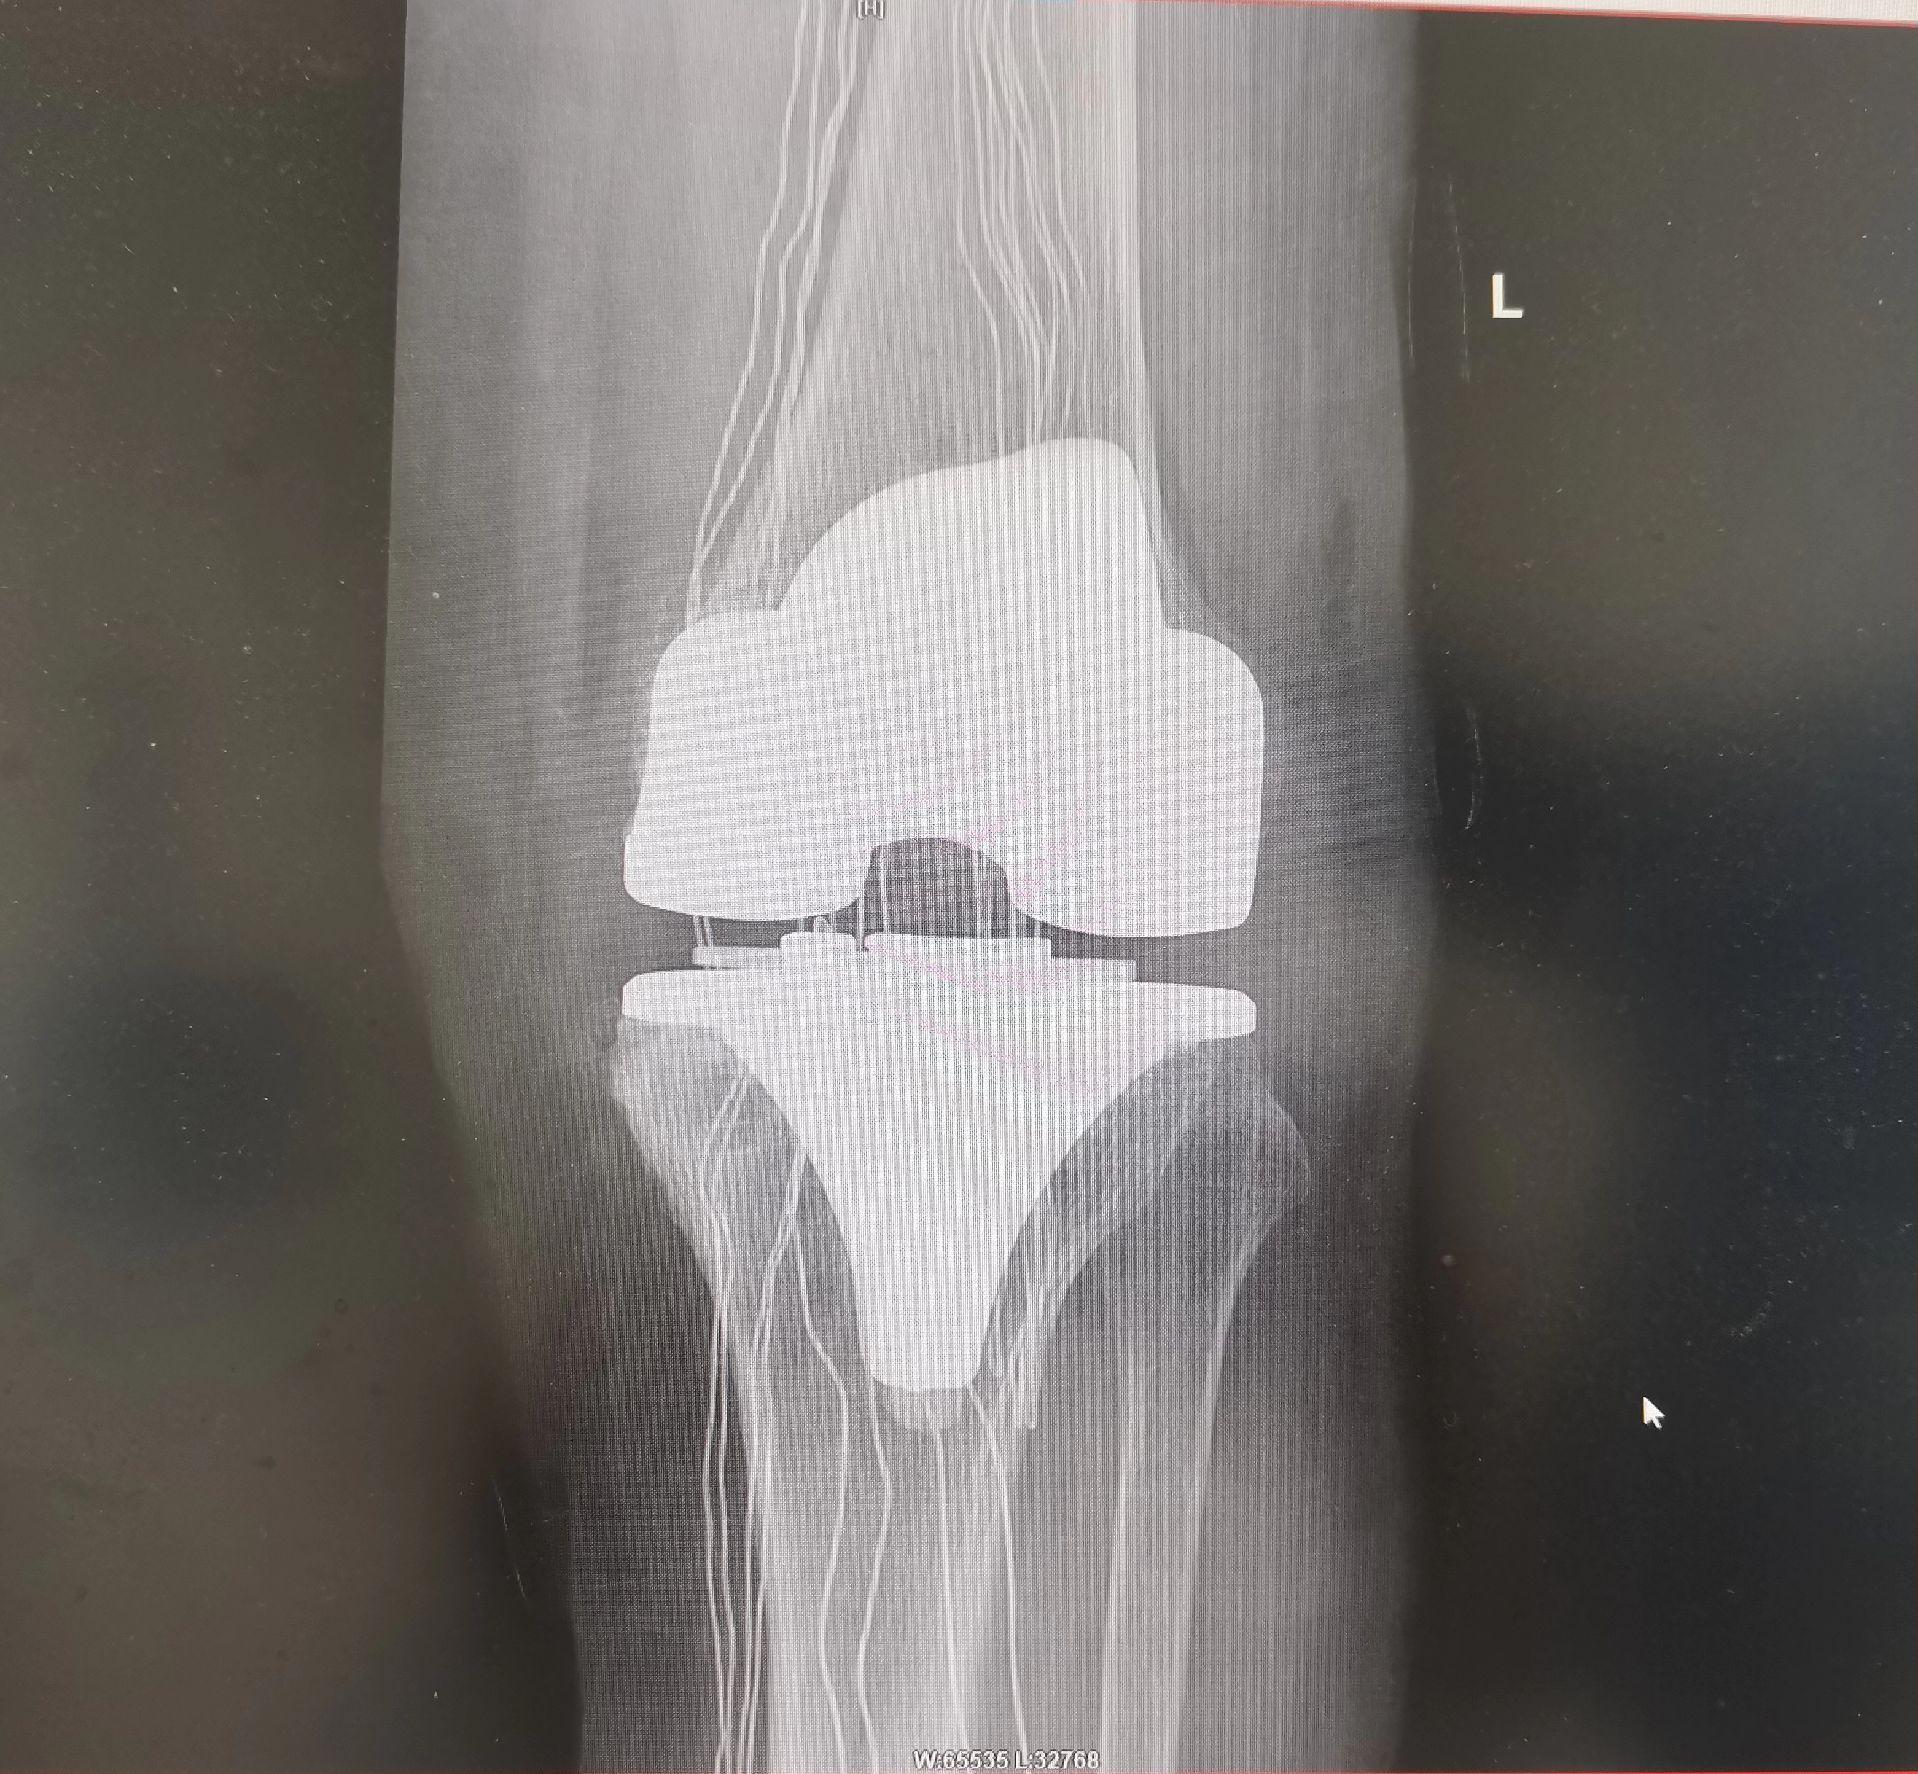

膝关节置换TKA.骨关节炎重度内翻合并屈曲挛缩畸形,无法行走,一期行双侧TKA,愿每一位患者都能得到有效的治疗,都能早日恢复正常生活🌹